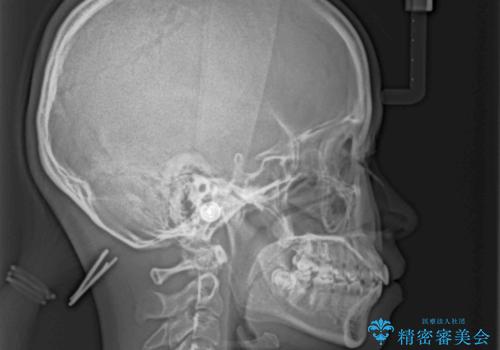

- 前歯の出っ歯と口元の閉じにくさを気にして来院された患者様です。

口元を積極的に引っ込めるために、上下左右の小臼歯4本を抜歯することとしました。

4本の歯を抜歯したことで、飛び出していた口元が引っ込み、横顔が大きく改善されました。